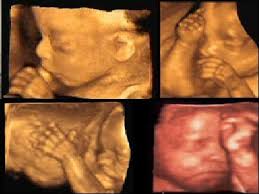

ROMA, quarta-feira, 25 de abril de 2012 (ZENIT.org) - A partir de 1º de julho, as mulheres de Virgínia, EUA, terão que fazer uma ecografia se quiserem abortar. Serão isentas apenas as mulheres que sofreram estupro ou incesto, conforme informações do site francês Gènéthique, da Fundação Jérôme Lejeune.

A Virgínia é o

oitavo estado a impor este procedimento antes de um aborto. As mulheres

podem se recusar a ver a imagem do feto e ouvir as batidas do seu

coração, desde que reiterem a recusa por escrito. No entanto, não

poderão recusar o ultrassom.